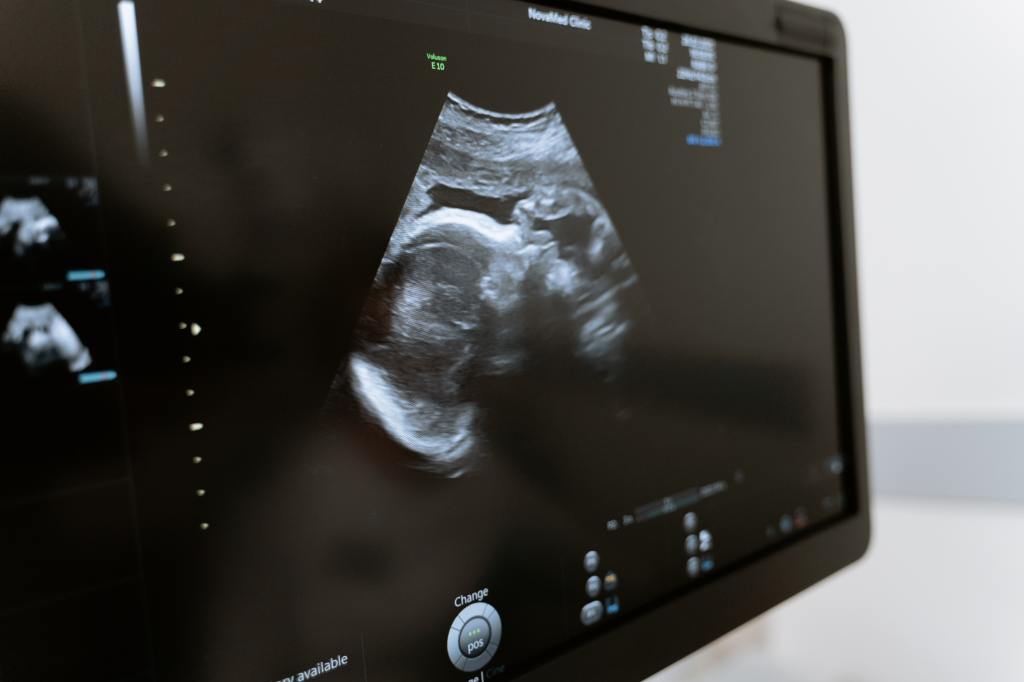

Furthermore, ultrasound is vital in estimating gestational age in the second and third trimester of pregnancy. This is very helpful in the management of preterm labour and ultrasound allows this diagnosis to be carried out successfully by non-obstetric specialists with a high degree of sensitivity [1]. Ultrasound also helps to diagnose multiple gestations, accurately follow up foetal growth, detect foetal anomalies, and placental location and implantation [2]. In addition to this, there have been literary reports of improved mother foetal bonding due to these scans [4].

It is a vital piece of equipment for the developing world as it helps to produce a more thorough differential diagnosis as well as helping to narrow down the diagnosis in order to create a better management plan. In Monrovia, Liberia a study showed that ultrasound changed the patient management in 62% of cases in the major tertiary care centre. Of which, the greatest impact was on patient management after the first trimester obstetric ultrasound [5].

In rural Zambia, over a 6 month training period 441 ultrasounds were performed with the main abnormal findings being non-vertex presentation (61%), multiple gestations (24%) and no foetal heart rate. This prompted change to 17% of the clinical decision-making and 100% of the midwives reported that ultrasound improved their practice and changed their management for the better [6]. This shows that not only can the Ultrasound machine help to increase medical accuracy and improve patient care but it also empowers the healthcare professionals who use it in order to make a more educated diagnosis.

To conclude, I have chosen the ultrasound machine as it helps to reduce maternal mortality by identifying risks early and adapting management plans accordingly. Furthermore, it helps to reduce both pre and peri natal mortality which alongside maternal mortality remains the biggest disparity between low income and high income countries. Finally, an ultrasound machine is multi-purpose and can be used as both a diagnostic and therapeutic tool.